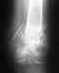

Переломы отчетливо видны. Насчет "за границей этот способ не применяют с 1965 года" - это просто чепуха несусветная, в то время метод Илизарова в СССР-то не везде еще применялся. А за границей, да при переломах пятки, его стали применять только лет 10-15 назад.